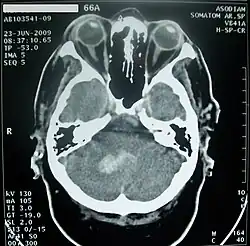

Нарушения мозгового кровообращения

Нарушения мозгового кровообращения в мозжечке могут проходить либо по ишемическому (I63 согласно МКБ-10[38]), либо по геморрагическому (I61.4 согласно МКБ-10[38]) типу.

Инфаркт (нарушение кровообращения по ишемическому типу) мозжечка возникает при закупорке позвоночной, базилярной или мозжечковой артерий и при обширном поражении сопровождается выраженными общемозговыми симптомами, нарушением сознания, Закупорка передней нижней мозжечковой артерии приводит к инфаркту в области мозжечка и моста, что может вызвать головокружение, шум в ушах, тошноту на стороне поражения — парез мышц лица, мозжечковую атаксию, синдром Горнера. При закупорке верхней мозжечковой артерии чаще возникает головокружение, мозжечковая атаксия на стороне очага[43].

Кровоизлияние в мозжечок обычно проявляется головокружением, тошнотой и повторной рвотой при сохранении сознания. Больных часто беспокоит головная боль в затылочной области, у них обычно выявляются нистагм и атаксия в конечностях. При возникновении мозжечково-тенториального смещения или вклинении миндалин мозжечка в большое затылочное отверстие развивается нарушение сознания вплоть до комы, геми- или тетрапарез, поражения лицевого и отводящего нервов[43].